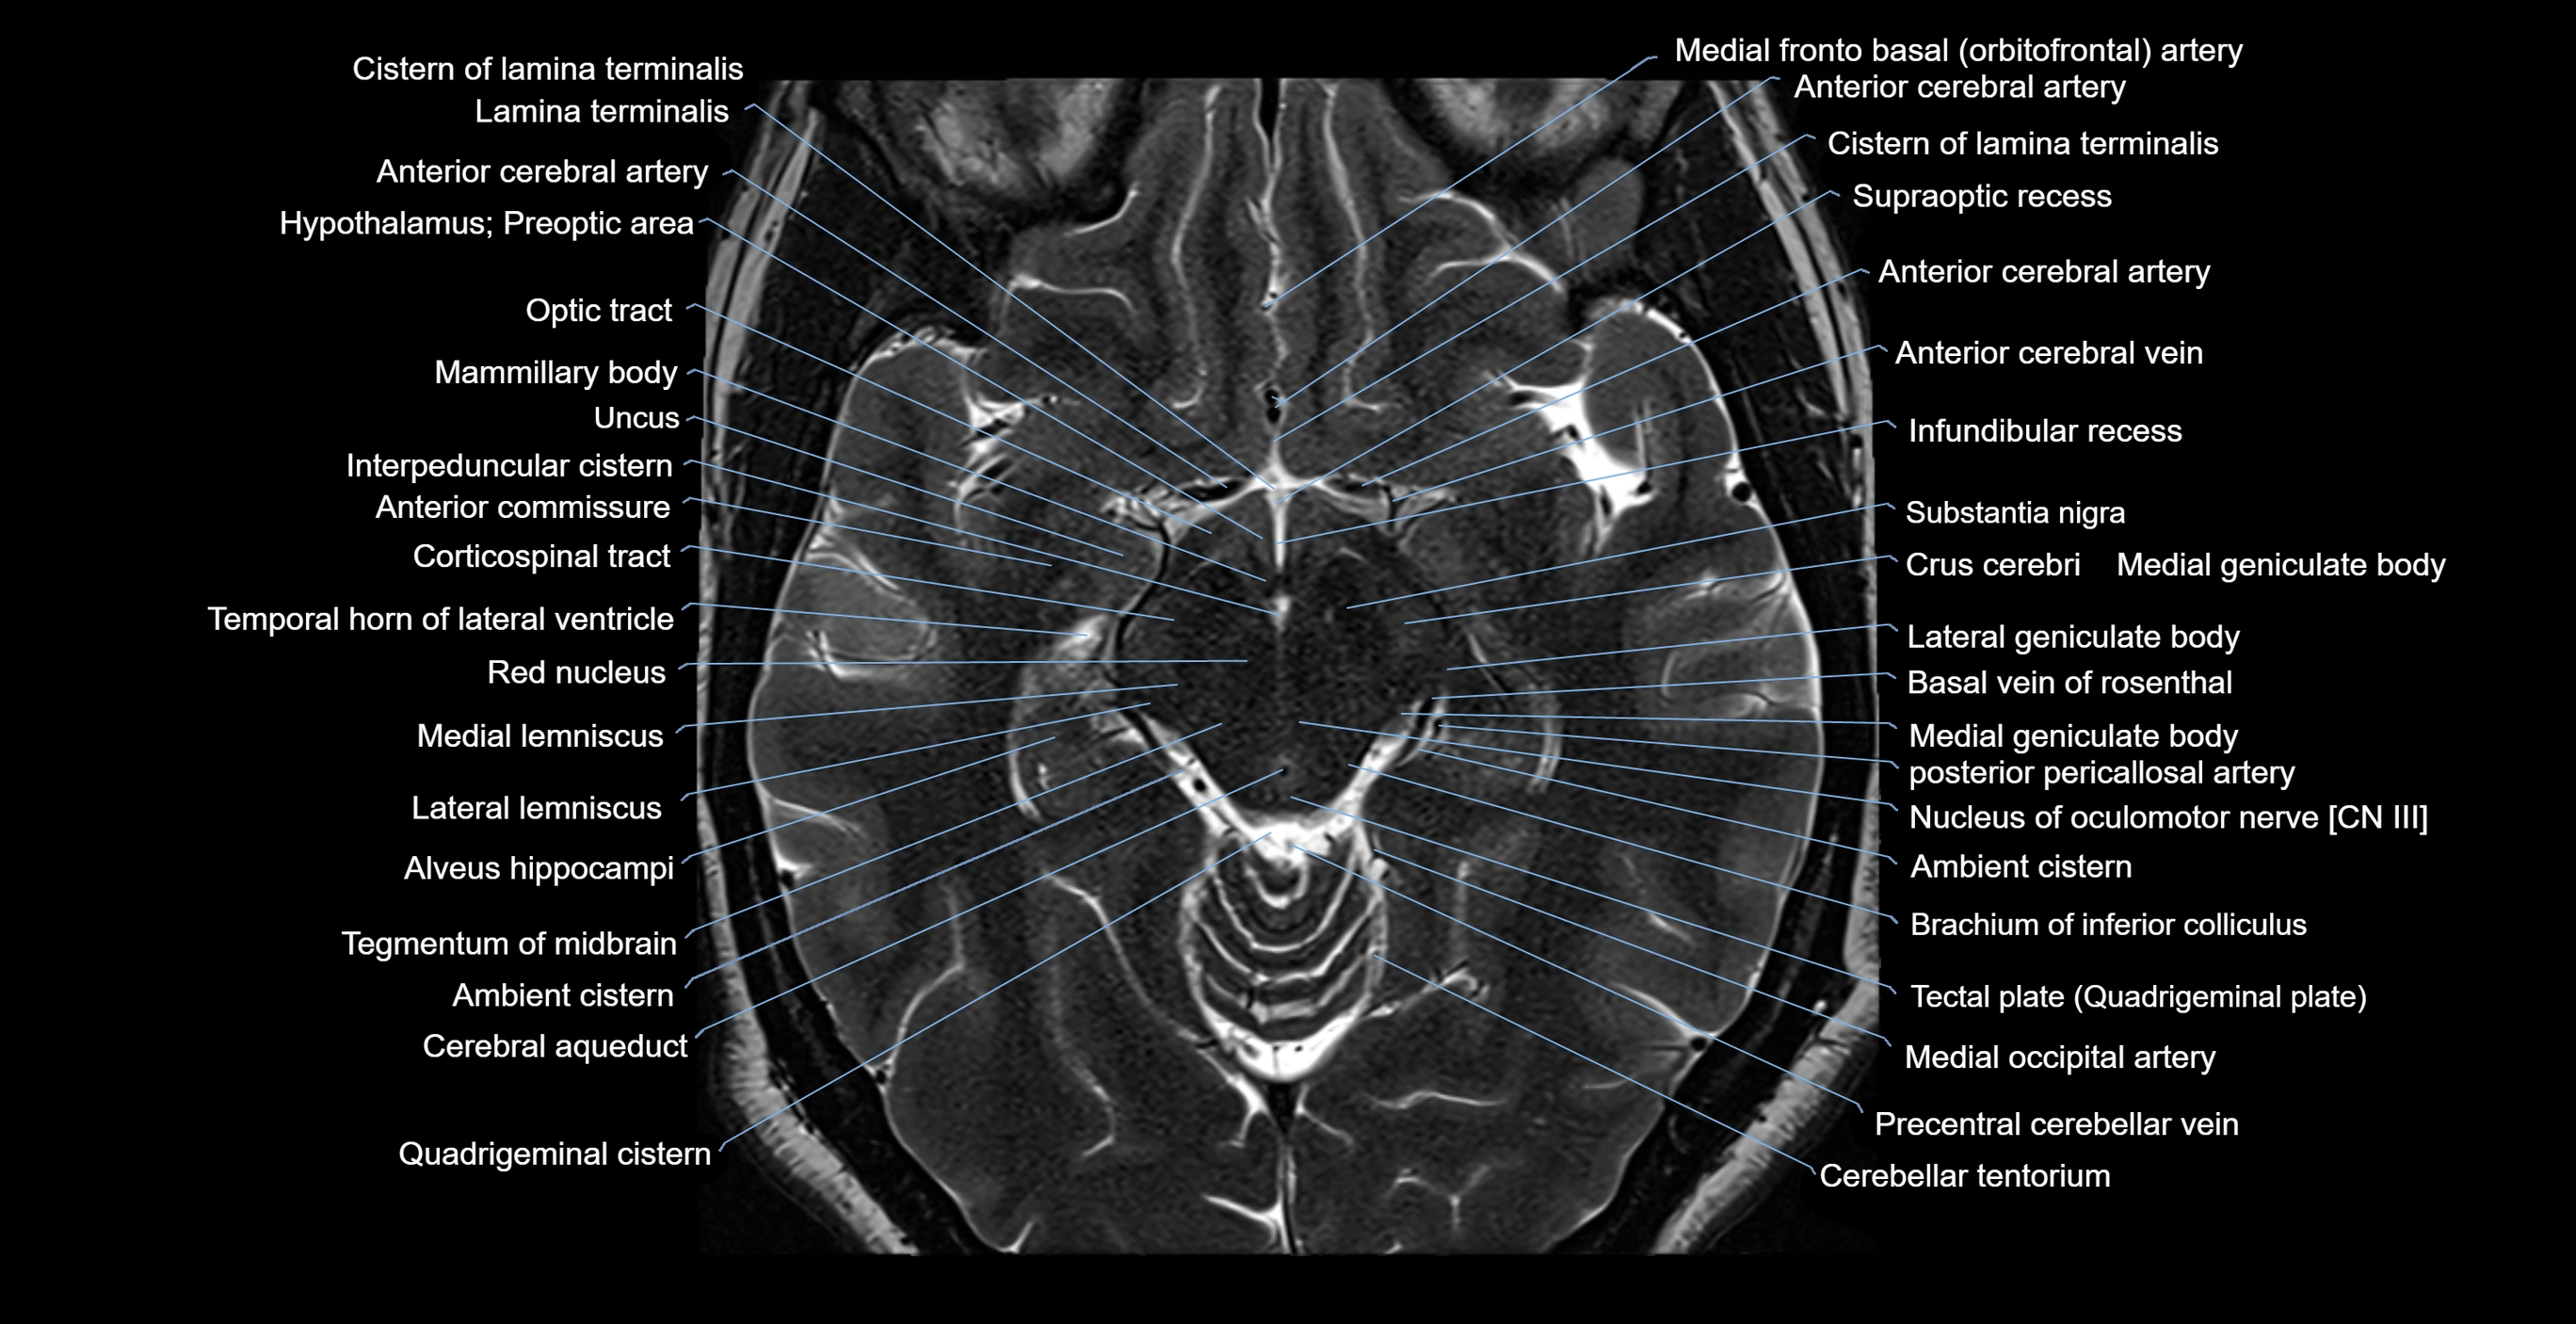

- Ambient cistern

- Anterior commissure

- Brachium of inferior colliculus

- Cerebral aqueduct

- Cerebral crus

- Corticospinal tract

- Crus cerebri

- Interpeduncular Cistern

- Lateral geniculate body

- Lateral lemniscus

- Mammillary body

- Medial geniculate body

- Medial lemniscus

- Nucleus of oculomotor nerve

- Quadrigeminal cistern

- Red nucleus

- Substantia nigra

- Tegmentum of midbrain

- Temporal horn of lateral ventricle

- Uncus